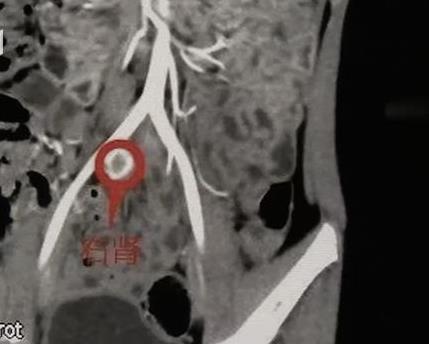

最終經過CT增強檢查,在她的右側盆腔發現了一個蠶豆大小的、功能很微弱的腎臟。

深圳市兒童醫院泌尿外科主治醫師張應添:「異位腎在盆腔這個位置,並且發育不好,它的功能還是有一點,但形態跟正常的左腎相比完全不一樣。」